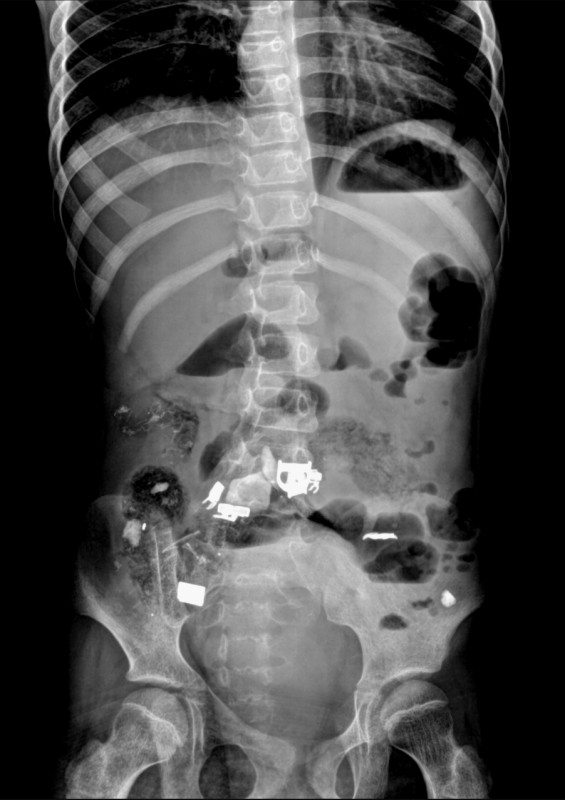

В Актау хирурги детской областной больницы извлекли из желудка 12-летней девочки-инвалида клок волос, ручку, скотч и кусок железа, передает Tengrinews.kz со ссылкой на Управление здравоохранения Мангистауской области.

Ребенка, который страдает ДЦП и задержкой психического развития, экстренно госпитализировали с жалобами на боли в животе и рвоту. Врачи провели всестороннее обследование организма, рентген показал инородные предметы в брюшной полости. Инцидент произошел в феврале, но известно о нем стало только сейчас.

"Благодаря оперативному вмешательству врачей, в ходе операции в кишечнике девочки благополучно обнаружены и вытащены инородные тела - железо, ручка, скотч, волосы", - сообщили в пресс-службе областного управления здравоохранения.

Осложнений в послеоперационном периоде не было. Ребенок в удовлетворительном состоянии.